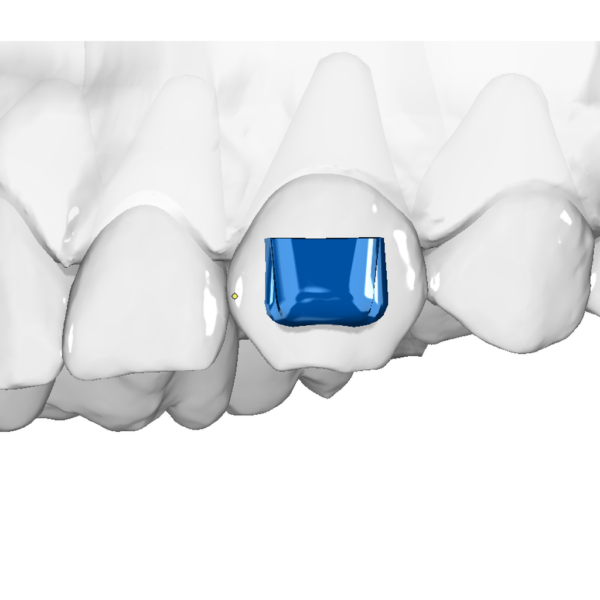

Aligner Accessories (STL Templates for Enhanced Aligner Therapy)

Clear aligners are powerful—but with the right accessories, they become truly versatile. This category offers STL templates for attachments and add-ons that enhance biomechanics, giving orthodontists greater control and precision in aligner therapy.

✔ Multipurpose attachments: e.g. SASH for difficult movements

With these accessories, aligners can achieve movements that are often difficult or unpredictable on their own—transforming them into a comprehensive orthodontic tool rather than just an esthetic appliance.